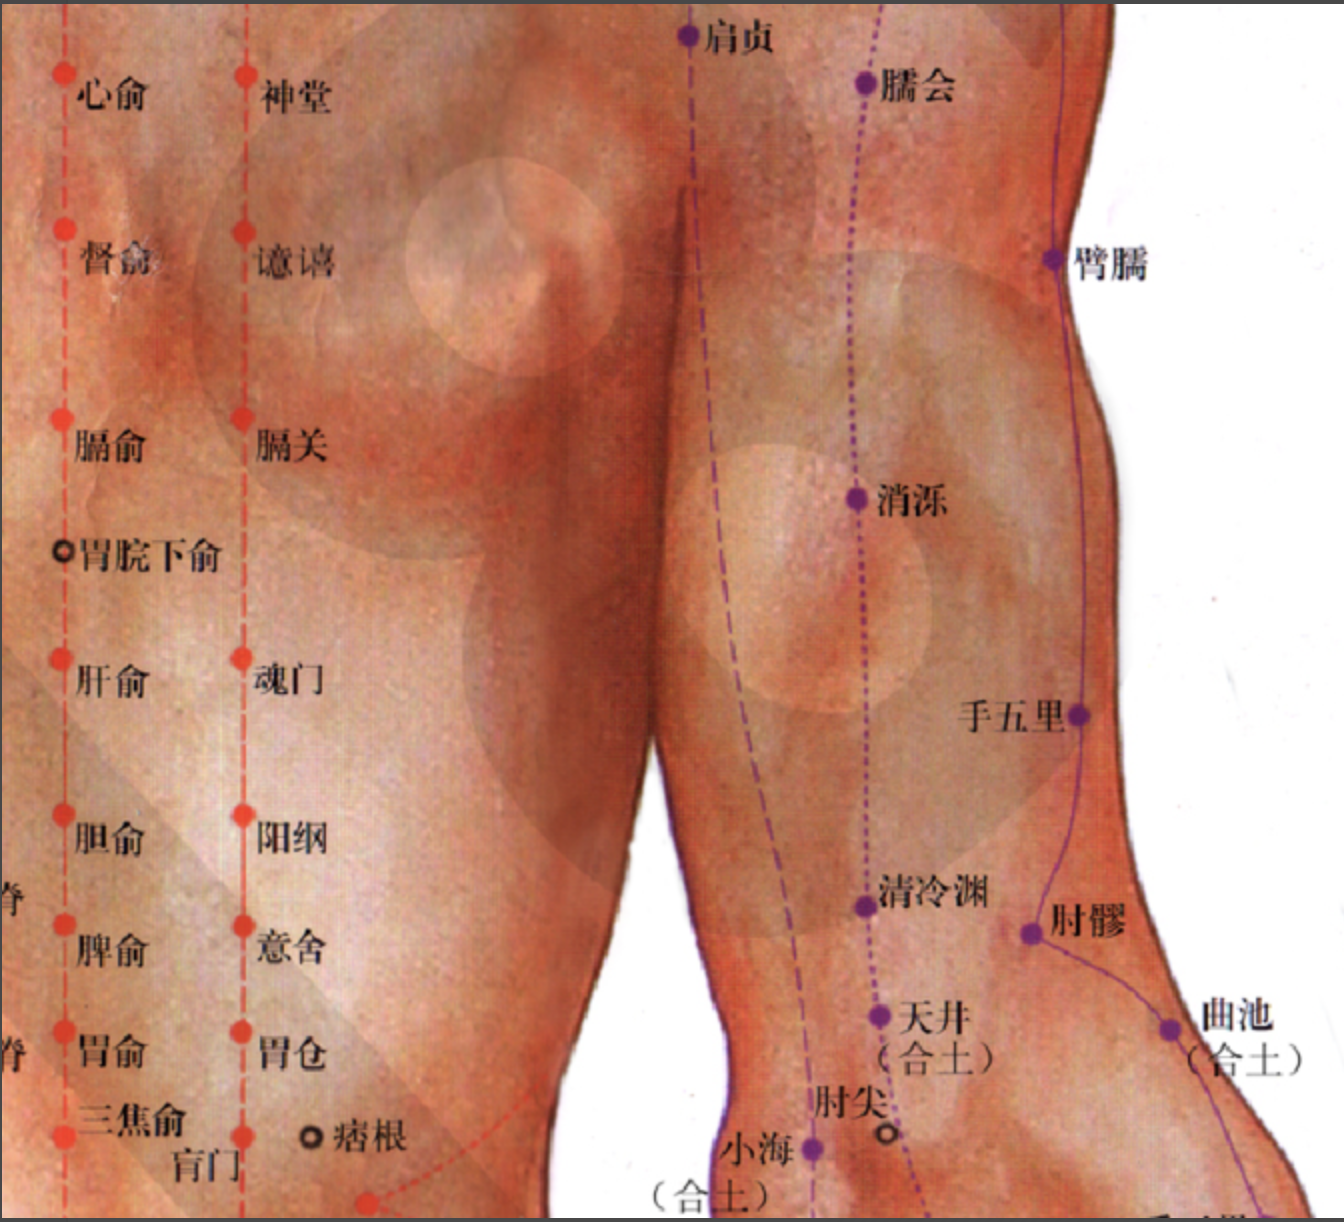

【(六)手太阳小肠经(图10-24-1)】

2、歌诀 手太阳经小肠穴,少则先行小指末,前谷后溪腕骨间,阳谷须同养老列,支正小海上肩贞,臑(nào)俞天宗秉风合,曲垣肩外复肩中,天窗循次上天容,此经穴数一十九,还有颧髎(liáo)入听宫。

3、经脉循行 起于手小指外侧端(少泽),沿手背外侧至腕部直上沿前臂外侧后缘,经尺骨鹰嘴与肱骨内上髁之间,出于肩关节,绕行肩胛部,交于大椎(督脉)向下入缺盆部联络心脏,沿食管过膈达胃,属于小肠。

缺盆部支脉:沿颈部上达面颊,至目外眦(zì),转入耳中(听宫)。

颊部支脉:上行目眶下,抵于鼻旁,至目内眦(睛明)、交于足太阳膀胱经。

4、主要病候 少腹痛、腰脊痛引睾丸、耳聋、目黄、颊肿、咽喉肿痛、肩臂外侧后缘痛等。

5、主治概要 主治头、项、耳、目、喉咽病、热病、神志病及经脉循行部位的其他病证。

天宗

【定位】 在肩胛部,当岗下窝中央凹陷处,与第 4 胸椎相平。

【主治】 肩胛疼痛,气喘,乳痈。

【配伍】 配肩外俞治肩胛痛,配膻中、足三里治乳痈。

【刺灸法】 直刺或斜刺 0.5 ~ 1 寸。

秉风

【定位】 在肩胛部,岗上窝中央,天宗直上,举臂有凹陷处。

【主治】 肩胛疼痛,上肢酸麻。

【配伍】 配天宗治肩胛疼痛。

【刺灸法】 直刺或斜刺 0.5 ~ 2 寸。

【附注】 手三阳与足少阳经交会穴。

【(七)足太阳膀胱经(图 10-25-1)】

2、歌诀 足太阳经六十七,精明目内红肉藏,攒竹眉冲与曲差,五处上寸半承光,通天络却玉枕昂,天柱后际大筋外,大杼(zhù)背部第二行,风门肺俞厥阴四,心俞督俞膈俞强,肝胆脾胃俱挨次。三焦肾气海大肠,关元小肠到膀胱,中膂(lǚ)白环仔细量,自从大杼至白环,各各节外寸半长,上髎次髎中复下,一空二空腰髁当,会阳阴尾骨外取,附分侠脊第三行,魄户膏肓与神堂。噫嘻膈关魂门九,阳纲意舍仍胃仓。肓门志室胞肓续,二十椎下秩边场,承扶臀横纹中央,殷门浮郗到委阳,委中合阳承筋是,承山飞扬踝附阳。昆仑仆参连申脉,金门京骨束骨忙,通谷至阴小指旁。

3、经脉循行 起于目内眦,上额交会于于巅顶(百会)。

风门

【定位】 在背部,当第 2 胸椎棘(jí)突下,旁开 1.5 寸。

【主治】 伤风,咳嗽,发热头痛,项强,胸背痛。

【配伍】 配肺俞、大椎治咳嗽、气喘,配合谷治伤风咳嗽。

【刺灸法】 斜刺 0.5 ~ 0.8 寸。

【附注】 足太阳经与督脉交会穴。

肺俞

【定位】 在背部,当第 3 胸椎棘突下,旁开 1.5 寸。

【主治】 咳嗽,气喘,吐血,骨蒸,潮热,盗汗,鼻塞。

【配伍】 配风门治咳嗽喘,配合谷、迎香治鼻疾。

【刺灸法】 斜刺 0.5 ~ 0.8 寸。

【附注】 肺的背俞穴。

心俞

【定位】 在背部,当第 5 胸椎棘突下,旁开 1.5 寸。

【主治】 心痛,惊悸,咳嗽,吐血,失眠,健忘,盗汗,梦遗,癫痫。

【配伍】 配巨阙、内关治心痛,惊悸,配内关、神门治失眠、健忘。

【刺灸法】 斜刺 0.5 ~ 0.8 寸。

【附注】 心的背俞穴。

膈俞

【定位】 在背部,当第 7 胸椎棘突下,旁开 1.5 寸。

【主治】 呕吐,呃逆,气喘,咳嗽,吐血,潮热,盗汗。

【配伍】 配内关、足三里治呕吐、呃逆,配足三里、血海、膏肓治贫血。

【刺灸法】 斜刺 0.5 ~ 0.8 寸。

【附注】 (1)八会穴之一,血会膈俞。(2)参考资料:据报道,用人工放血造成家兔的贫血状态(红细胞在 4 × 10 ** 12 / L以下,血红蛋白在 65 g/L以下),针刺“膈俞”“膏肓”,结果与对照组相比,提前纠正了贫血状态,迅速恢复正常。

肝俞

【定位】 在背部,当第 9 胸椎棘突下,旁开 1.5 寸。

【主治】 黄疸,胁痛,吐血,目赤,目眩,雀目,癫狂痫,脊背痛。

【配伍】 配支沟、阳陵泉治胁痛,配太冲治目眩。

【刺灸法】 斜刺 0.5 ~ 0.8 寸。

【附注】 肝的背俞穴。

胆俞

【定位】 在背部,当第 10 胸椎棘突下,旁开 1.5 寸。

【主治】 黄疸,口苦,胁痛,肺痨,潮热。

【配伍】 配阳陵泉、太冲治胆道疾病。

【刺灸法】 斜刺 0.5 ~ 0.8 寸。

【附注】 胆的背俞穴。

脾俞

【定位】 在背部,当第 11 胸椎棘突下,旁开 1.5 寸。

【主治】 腹胀,黄疸,呕吐,泄泻,痢疾,便血,水肿,背痛。

【配伍】 配足三里治腹胀、便秘。

【刺灸法】 斜刺 0.5 ~ 0.8 寸。

【附注】 脾的背俞穴。

胃俞

【定位】 在背部,当第 12 胸椎棘突下,旁开 1.5 寸。

【主治】 胸胁痛,胃脘痛,呕吐,腹胀,肠鸣。

【配伍】 配中脘、梁丘治胃痛。

【刺灸法】 斜刺 0.5 ~ 0。8 寸。

【附注】 胃的背俞穴。